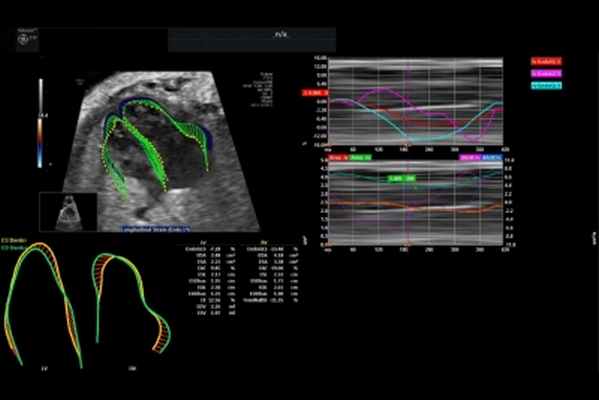

Цель исследования. Изучение возможностей применения эхокардиографии (ЭхоКГ) с контрастным усилением и количественной оценкой перфузии миокарда левого желудочка (ЛЖ) у пациентов с крупноочаговым постинфарктным кардиосклерозом.

Материал и методы. Обследованы 15 мужчин (возраст от 42 до 72 лет) с патологическим зубцом Q в 2 отведениях электрокардиограммы и более. Количественную оценку перфузии миокарда ЛЖ осуществляли при помощи расчета тканевой интенсивности ультразвукового сигнала от миокардиальных сегментов ЛЖ на фоне внутривенного введения контрастного препарата. Динамику изменения интенсивности перфузии миокарда (A4, дБ) оценивали как разницу между значениями интенсивности ультразвукового сигнала в миокардиальном сегменте до принудительного разрушения контрастного вещества (до нанесения «flash») и в период восполнения пузырьков контрастного агента на 4-й кардиоцикл (после нанесения «flash»). Измерения осуществляли в 16 сегментах ЛЖ во временной отрезок, соответствующий конечному диастолическому периоду кардиоцикла. С целью верификации крупноочагового фиброза миокарда ЛЖ всем обследуемым выполнена контрастная магнитно-резонансная томография (МРТ) сердца с оценкой наличия фиброзных изменений в миокардиальных сегментах. Учитывали наличие или отсутствие признаков фиброза 50% и более толщины каждого из изучаемых сегментов.

Результаты. Проведена оценка динамики перфузии и фиброзных изменений в 240 миокардиальных сегментах. Медиана A4 составила 1 (от –20 до 10) дБ. МРТ позволила выявить 82 сегмента с крупноочаговыми фиброзными изменениями. Оценена эффективность диагностического теста (количественной перфузионной ЭхоКГ с контрастным усилением c оценкой A4) по выявлению фиброзных изменений в миокарде. Анализ ROC-кривой показал хорошее качество модели: AUC 0,787 при 95% доверительном интервале от 0,730 до 0,837 (p<0,01); чувствительность 82,9%, специфичность 75,3%. Точка отсечения для A4 оказалась равной –1.

Выводы. Новый подход к количественной контрастной оценке перфузии миокарда позволяет с высокой эффективностью выявлять нарушения перфузии у пациентов с крупноочаговым постинфарктным кардиосклерозом.